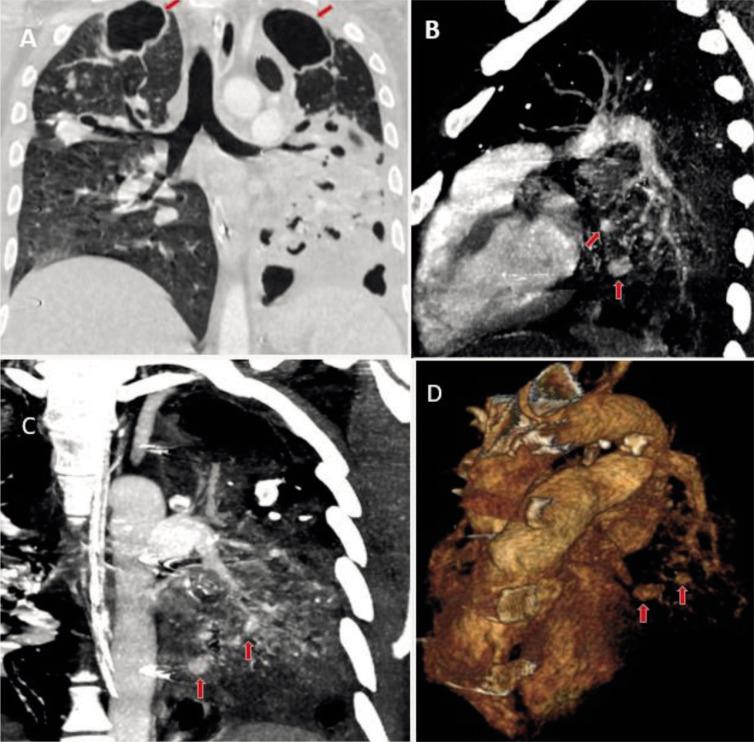

Hemoptysis is defined as coughing out of blood. Pulmonary tuberculosis is the most common cause of hemoptysis in tuberculosis-endemic countries like India. Rasmussen aneurysm is a pseudoaneurysm arising from the pulmonary artery adjacent to or within a tuberculous cavity. Chest radiographs, chest computed tomography angiography (CTA), and digital subtraction angiography (DSA) are the imaging tools for evaluating a case of hemoptysis.

CASE

A 32-year-old man with a history of pulmonary tuberculosis presented with complaints of recurrent hemoptysis. On imaging evaluation, multiple pulmonary artery pseudoaneurysms were seen in the left lung. The patient was shifted to the DSA lab and the pseudoaneurysms were subsequently treated by endovascular coil embolization. Hemoptysis resolved following the procedure and the patient was again started on anti-tubercular therapy.

Endovascular coiling is minimally invasive, safe, and effective management of multiple Rasmussen aneurysms for preventing possible torrential blood loss and unfortunate death.